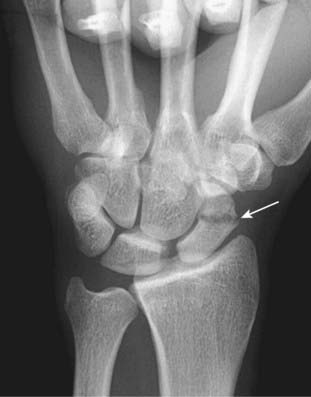

Figure 22-25 Scaphoid fracture.

Scaphoid fractures are common. They are suspected clinically if there is tenderness in the anatomic snuff box after a fall on an outstretched hand. Look for linear fracture lines on special angled views of the scaphoid (solid white arrow). Fractures across the waist of the scaphoid can lead to avascular necrosis of proximal pole of that bone.

Figure 22-26 Avascular necrosis of the proximal pole of the scaphoid.

A close-up frontal view of the wrist demonstrates that the proximal pole of the scaphoid (solid black arrow) is denser than the distal pole (solid white arrow). There is a fracture through the waist of the scaphoid (dotted white arrow). Because of the peculiar blood supply of the scaphoid (from distal to proximal), fractures through the waist may interrupt the proximal blood supply while the other bones of the wrist, having normal blood supply, become demineralized. This makes the proximal pole of the scaphoid appear denser relative to the other bones of the wrist.